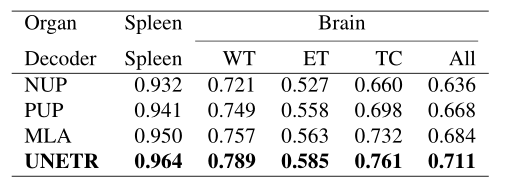

在表2中,在MSD数据集上比较了UNETR与CNN以及基于Transformers的方法在脑肿瘤和脾脏分割任务中的性能。在脑分割方面,UNETR在所有语义类上的平均表现比最接近的基线高出1.5%。特别是,UNETR在分割肿瘤核心(TC)分区域方面表现得相当好。同样,在脾脏分割方面,UNETR在Dice评分方面的表现比最佳竞争方法高出至少1.0%。

表2:定量比较了MSD数据集在脑肿瘤和脾脏分割任务中的分割性能。WT、ET和TC分别表示全肿瘤、增强肿瘤和肿瘤核心子区域。

解码器的选择:在表3中,通过比较UNETR和其他解码器架构在两个MRI和CT模式的代表性分割任务上的性能来评估解码器的有效性。在这些实验中,使用UNETR的编码器,但用朴素向上采样(NUP)、渐进向上采样(PUP)和多尺度聚合(MLA)的3D对应版本替换解码器。观察到这些解码器架构产生次优性能,尽管MLA略微优于NUP和PUP。对于脑肿瘤的分割,UNETR比MLA、PUP和NUP解码器的平均准确率分别高出2.7%、4.3%和7.5%。同样,对于脾脏分割,UNETR外形成的MLA、PUP和NUP分别为1.4%、2.3%和3.2%。

表3:解码器架构对分割性能的影响。(Naive UpSampling、Progressive UpSampling and Multi-scale Aggregation)